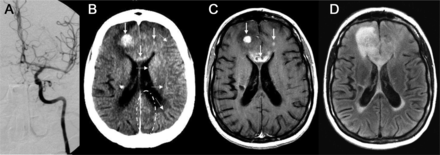

43岁的男人(A)与多形性胶质母细胞瘤(GBM)接受了血脑屏障的破坏(BBBD)通过左椎动脉导管造影(A)。在30分钟,对比增强CT表现,说明增强两国后大脑皮层的动脉(PCA)分布(虚线箭头表示正常皮质增强左侧)与增强肿瘤边缘围绕正确的侧脑室后角的(箭头,b, c),指出在postcontrast t1加权磁共振成像(d)。一个34岁的男人(b)与“绿带运动”接受了右颈内动脉(ICA)导管BBBD (A),与合成右大脑中动脉(MCA)分布增强(虚线箭头,b),备件ACA分布(虚线轮廓,c);缺乏cross-filling注意到A1段ACA,以及正确的MCA,通过前动脉和缺乏沟通PCA皮质分布增强(a)。第二天,病人接受导管BBBD通过ICA左边,与示范的双边ACA皮质分布增强(虚线箭头,c),这可能是由于为两国留住好的cross-filling以及A1段正确的ACA、MCA,看到通过ICA (d)。